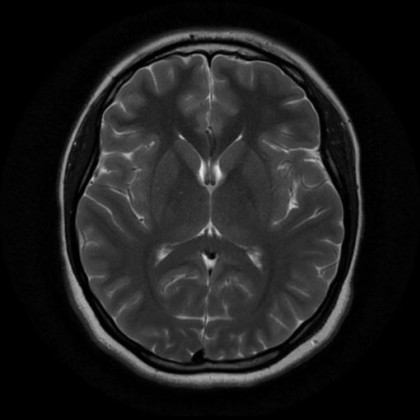

Специалисты из МГМУ имени Сеченова создали приложение, которое способно выявлять на МРТ-снимках опухоли головного мозга. Кроме того, искусственный интеллект способен определить локализацию и тип новообразования.

Одна из целей амбициозного проекта – снизить нагрузку на врачей-рентгенологов и повысить точность и эффективность ранней диагностики.

На данный момент точность определения – 97,1%.

На данный момент создан прототип приложения и серверная версия с готовым интерфейсом. Один из следующих шагов – привлечение данных из российских рентгенологических лабораторий для повышения точности работы.